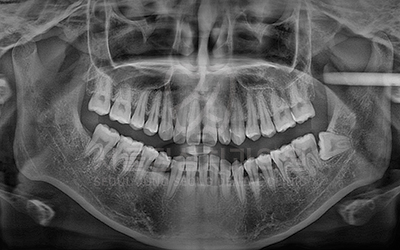

신경치료 케이스

• BEFORE

• AFTER